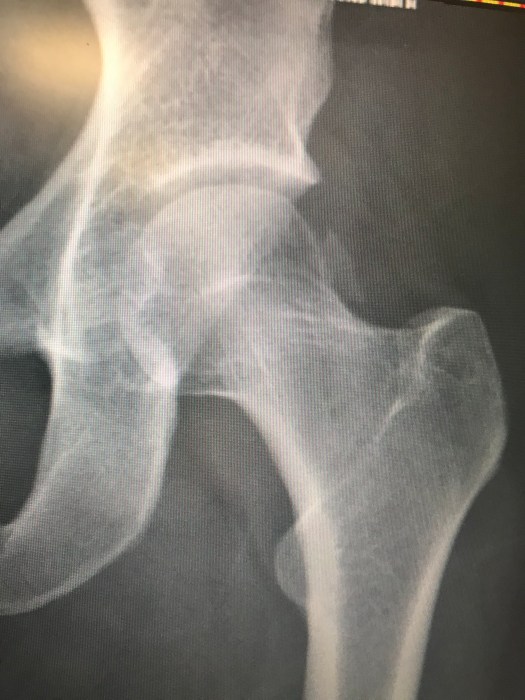

Not only was the left side of my body obliterated with a blown shoulder, multiple hits sustained from my neck to my tailbone, a heavily haematoma’d left buttock, a fractured pelvis, a dislocated hip, fracture to the head of the femur, a full tear of the MCL, a fractured tibial plateau, some sweet scars down my lumbar spine courtesy of the rocks I hit mid tumble….. and a head injury which was yet to raise its hand following a long period of unconsciousness post tumble. But if I was cleared to walk, then I was determined to start to hobble my way back to normal one step at a time.